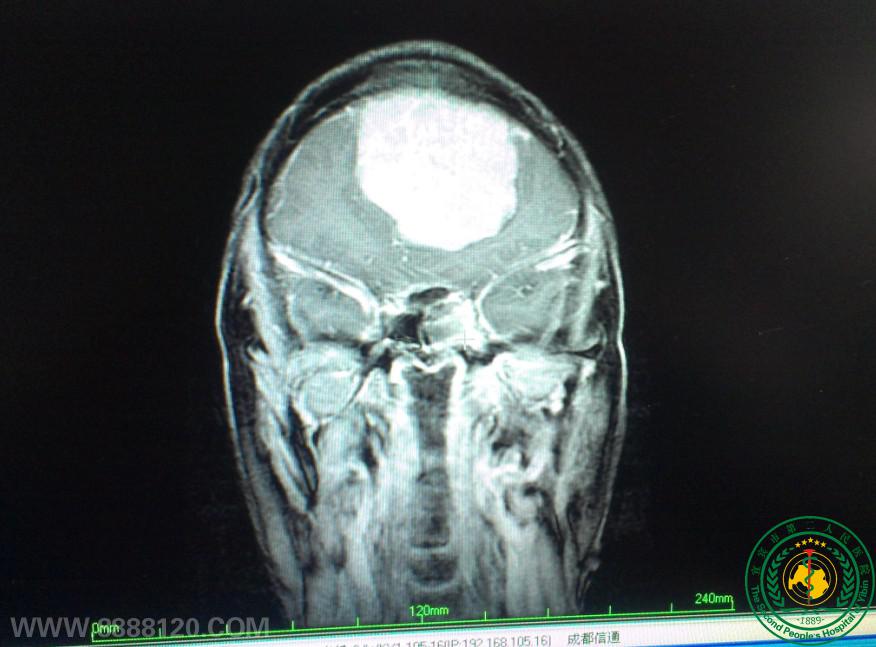

我科顺利完成颅内巨大脑膜瘤一例

我科顺利完成颅内巨大脑膜瘤一例5838